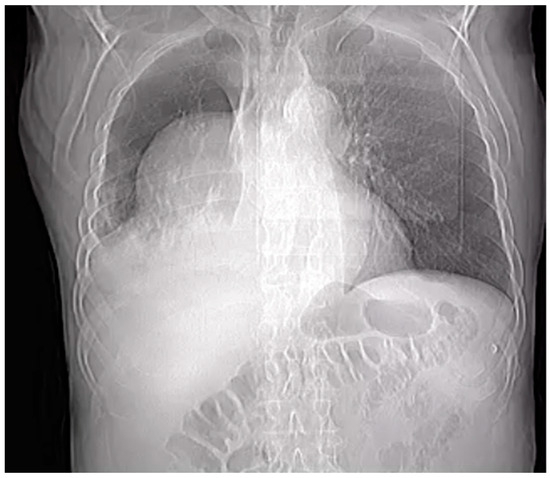

- Right pleural aortic false aneurysm (Figure 3): The most striking feature was the presence of an expansive false aneurysm within the right pleural cavity, measuring approximately 12.92 cm × 9.3 cm. The size and location of this pseudoaneurysm were unprecedented, introducing a challenge in terms of diagnosis and intervention.

- Megaesophagus: Notably, the imaging findings also uncovered a megaesophagus, a condition characterized by significant dilation of the esophagus. Although not the primary focus of intervention, its presence added another layer of complexity to the clinical scenario. The etiology of the megaesophagus remained to be elucidated.

- Compression of the lung: The false aneurysm within the right pleura had exerted a significant mass effect, resulting in the compression of surrounding structures, notably the lung. This compression had led to compromised ventilation of the lung, contributing to a concerning clinical picture.

- Potential lung infection (Empyema): The compromised lung, in part due to the mass effect of the false aneurysm, exhibited signs of infection. Imaging suggested the possible development of empyema. This provided a plausible explanation for the patient’s presenting symptom of hemoptysis.